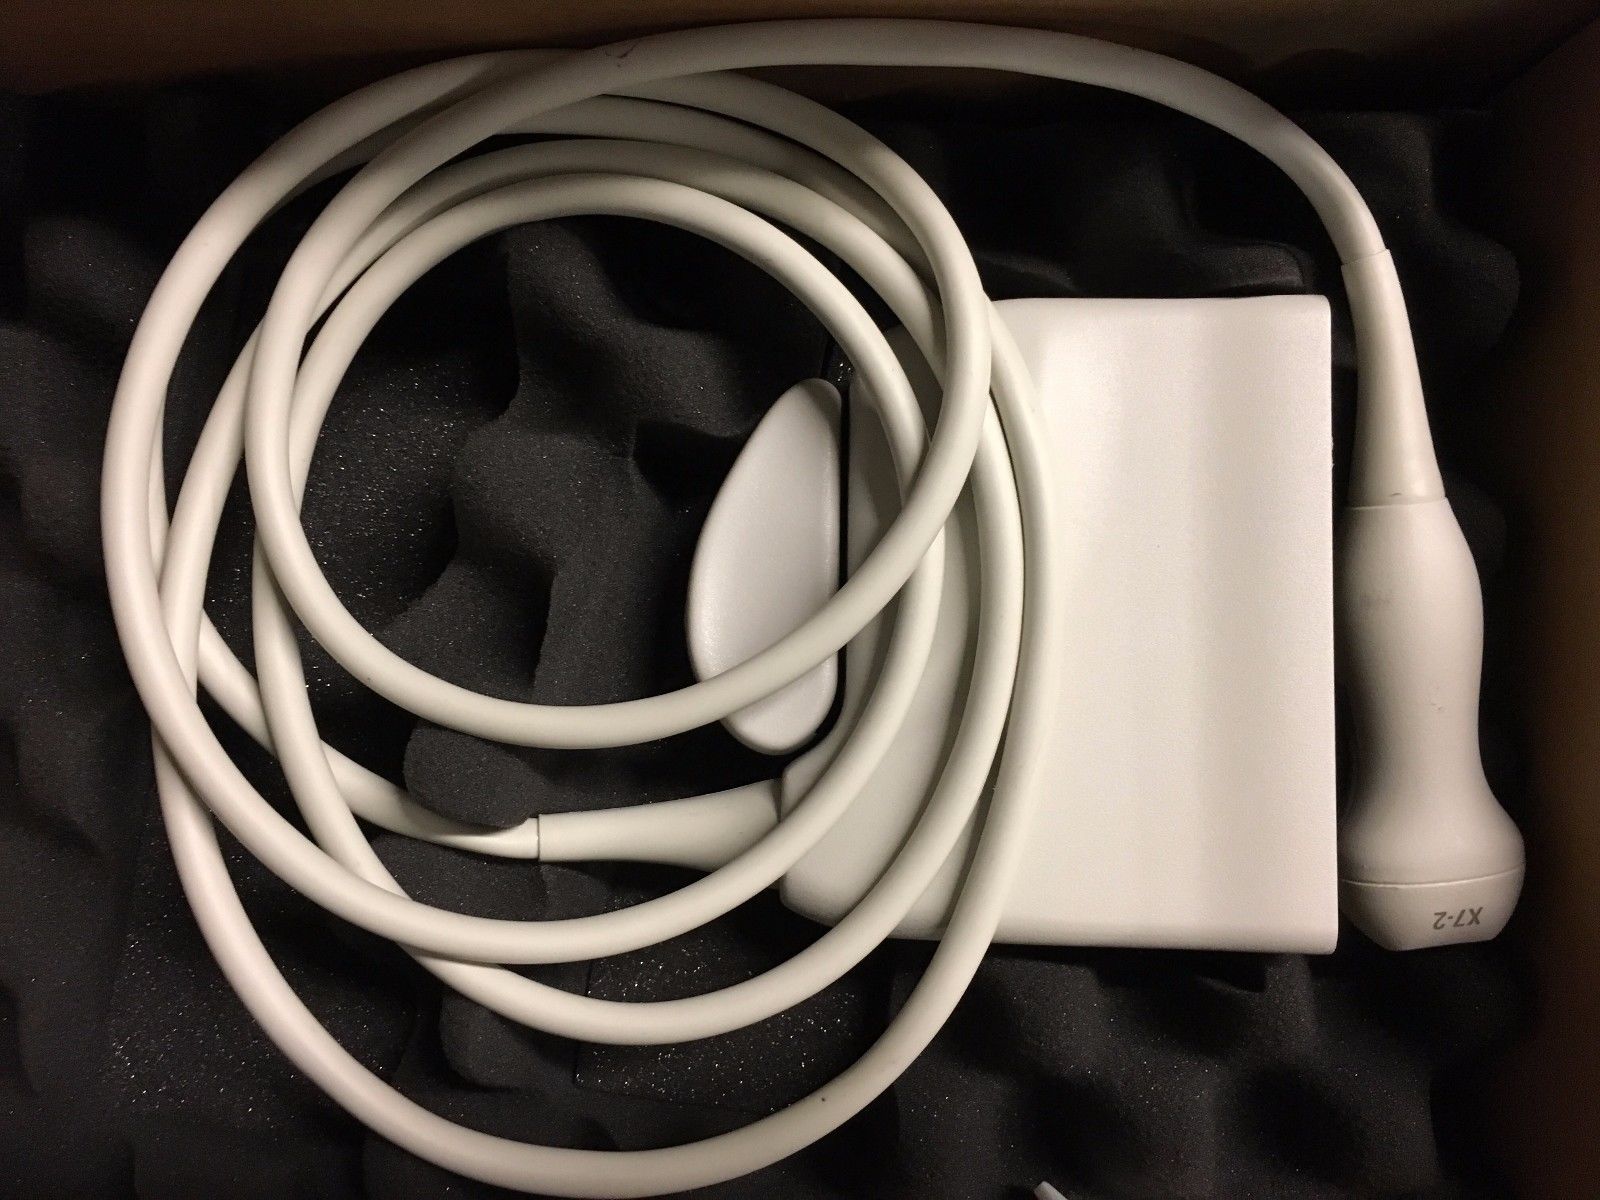

Philips X7-2 Ultrasound Probe Transducer

Sale price$ 1,392.60